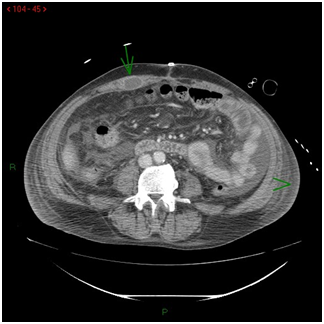

Brain scan showed a 9x6mm hypodense nodular lesion with peripheral rim enhancement in the cerebellar vermis that was consistent with an abscess. A small degree regression of the lung abscess was observed; and two abscesses (diameter of 47 and 48mm) in the right and left trapezius were seen on CT-thorax scan. CT-abdomen scan revealed little quantity of free intraperitoneal liquid, and two abscesses (23x14 and 20x20mm) in the right rectus and the right gluteus (Figure 3). Echocardiography was normal.

Figure 3 CT-abdomen scan: few quantity of free intraperitoneal liquid, and two abscesses (23x14 and 20x20 mm) in the right rectus and the right gluteus.